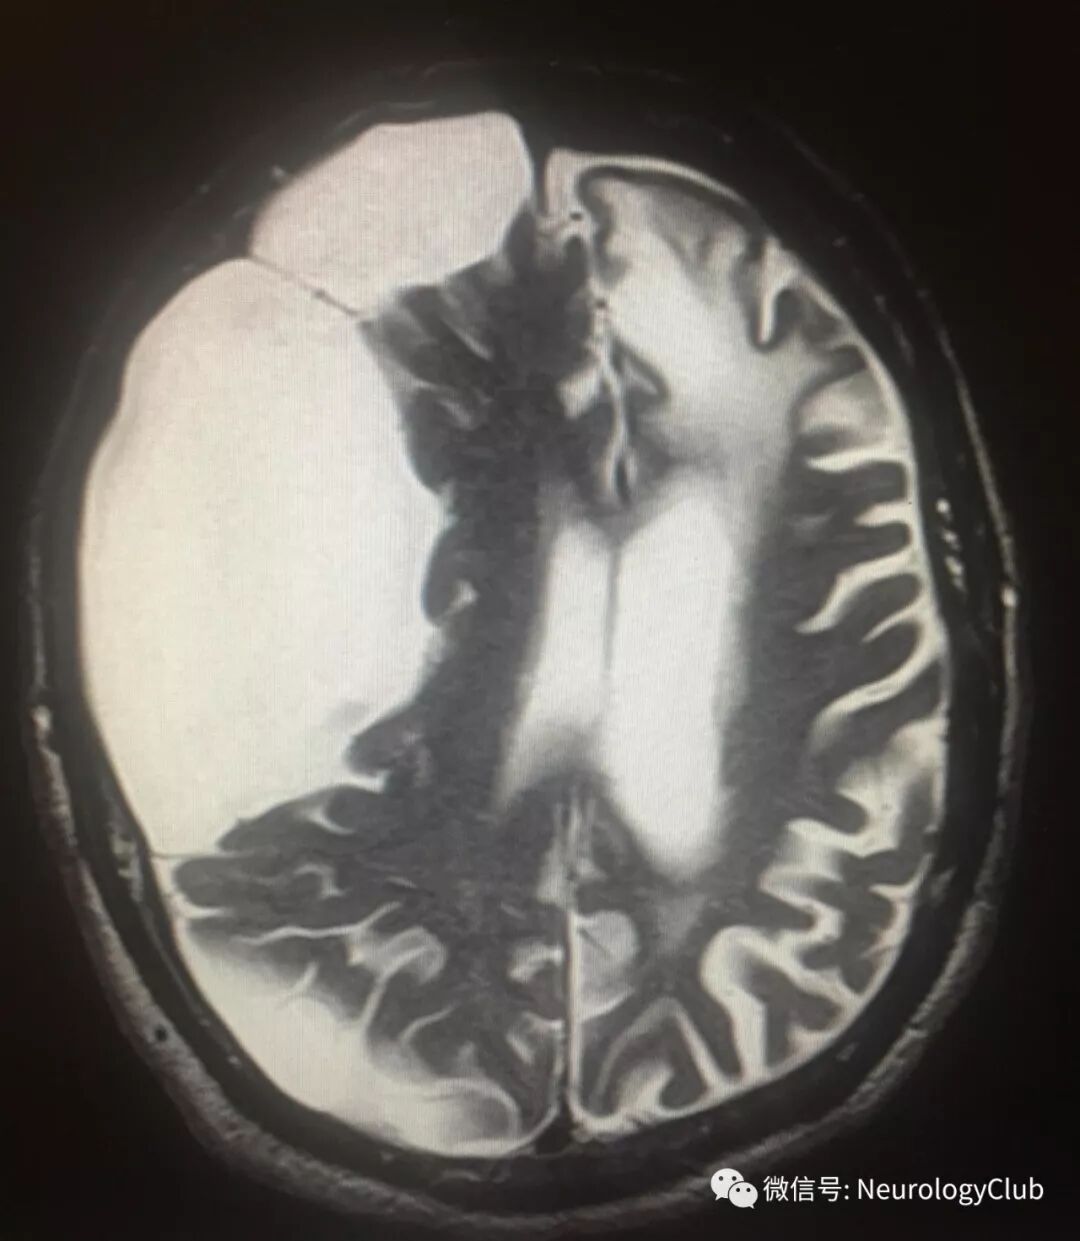

头颅MRI如下:

(图2:横断面T2WI可见右侧大脑半球囊性病灶;可见蛛网膜下腔分隔;占位效应明伴中线移位,达11mm)